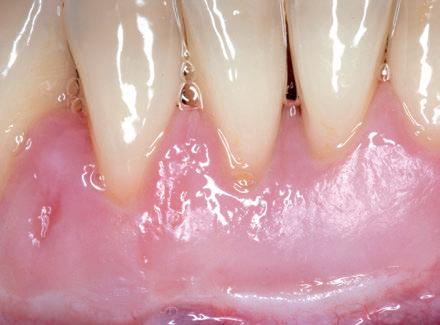

La gura nº2, muestra el tejido donante suturado al lecho receptor. El margen del injerto, se sitúa a nivel de la línea amelocementaria. La gura nº 3, muestra la cicatrización temprana a los dos

meses. Se puede apreciar una pérdida parcial del injerto en su porción coronal. Está descrito en la literatura cientí ca que en recesiones estrechas, cuando se logra un óptimo control del bio lm sobre la super cie radicular expuesta, la encía puede reptar y acabar por cubrir la parte de la raíz expuesta. Este fenómeno, que

suele desarrollarse durante el primer año, no es nada nuevo y ha sido descrito ampliamente en la literatura cientí ca con el término de inserción reptante. En la gura nº 4, se muestra el resultado al año. Se aprecia cómo el injerto ha reptado hasta cubrir completamente la super cie radicular. Pero deseo insistir nuevamente en la idea de que el resultado al año, tiene tan solo un valor relativo. ¿Esta inserción reptante se mantiene estable a lo largo de los años o por el contrario, tiene cierta tendencia a la recidiva? La gura nº 5, muestra el caso 25 años después. En este periodo, la paciente se ha sometido a un segundo tratamiento ortodóntico, para resolver una recidiva. Se puede comprobar que tanto la encía que reptó, como todo el injerto en su conjunto, se mantienen estables a lo largo del tiempo.

Fig 3: Cicatrización temprana. Se ha creado una dimensión volumétrica de tejido queratinizado adecuada, se ha profundizado el vestíbulo, pero se ha perdido una pequeña cantidad de tejido donante, quedando una pequeña porción de las raíces sin cubrir.

Fig 4: Resultado al año. Se ha producido el fenómeno de inserción reptante. La encía ha cubierto la totalidad de la super cie radicular expuesta. Compárese con la Fig 3. Pero, ¿se mantiene estable esta inserción reptante a lo largo de los años? Fig 5: Resultado a los 25 años. La encía obtenida por medio de la inserción reptante, se mantiene estable 25 años después.